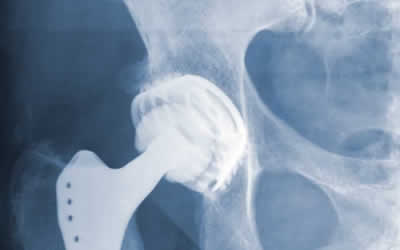

When corporations create and sell defective medical devices, it can have severe consequences for the patients they were intended to help. If a medical device does not operate as intended and instead causes further injury to a patient, the patient may have legal options for holding the manufacturer liable.